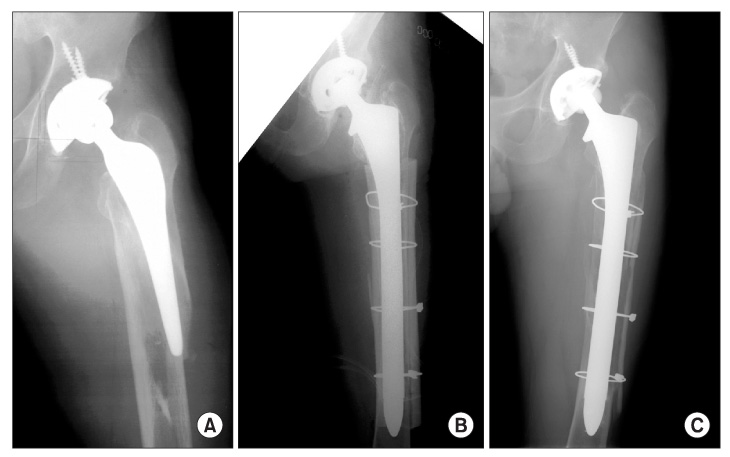

fracture (break) of the femur around your hip replacement